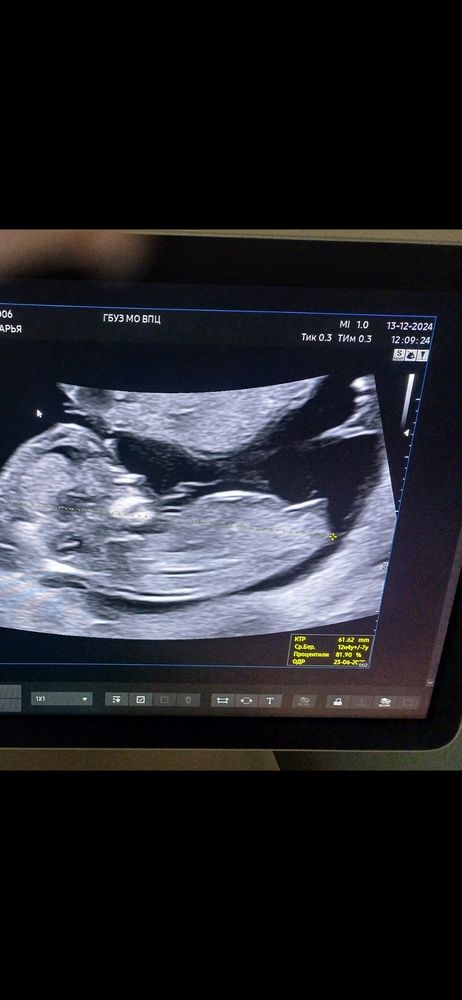

Мальчик или Девочка?)

Девочка 😍

Такой же снимок 90% девочка сказали)

Только вчера смотреоа в инсте узиста и это была девочка, у мальчиков лобная кость торчит на верх как писюнчик

Девочка 👧😍у пацанов верх торчит 😂👌

А я ставлю на мальчишку по тазобедренной кости

Лариса , ну, мне на скрининге сказали, что если тазобедренная кость цельная без "трещинок", то мальчик, а у девочек таз же формируется составной... Хотя на фото ещё раз смотрю, может и есть эти "растрешинки", как у девчонки

По бугорку каже ся что девочка

Ставлю на девочку у мальчика более вздернутый бугорок)

Скажите пожалуйста мальчик или девочка) Пол в 13 недель